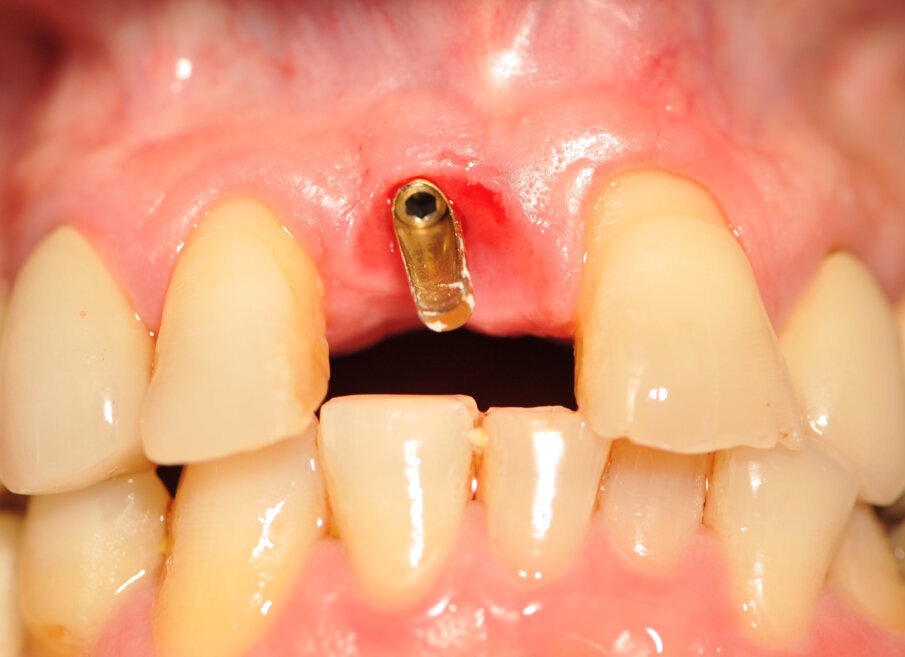

Paziente di sesso maschile di 60 anni di età giunto alla nostra osservazione per una edentulia parziale dovuta all’assenza dell’elemento 1,1. La situazione clinica è resa esteticamente e funzionalmente complicata dalla assenza dell’elemento 2,2 che considerato lo spostamento dei denti contigui comporta un aumentato spazio per la sostituzione protesica dell’elemento 1.1. Si effettua dopo rx di controllo il posizionamento di un impianto osteintegrato GTB diametro 3,6 x 9 mm ,con posizionamento, come da protocollo, 1,5 mm sottocrestale ed inserzione immediata di moncone easy abutment slim 3,4 x 7 mm altezza gengivale 3,5 mm. angolato a 10 gradi (Easy Abutment Slim – GTB Plan1Health Amaro, UD, Italy). Con l’ausilio di una cappetta easy si costruisce e si cementa, con tecnica extraorale, una corona provvisoria in resina acrilica con forma a pontic su elemento 1.1 in modo da eseguire un carico immediato e fornire al paziente una estetica immediata (Figg. 1-3). Dopo 12 settimane ad avvenuta osteointegrazione si provvede all’impronta definitiva eseguita a livello abutment con elastomero di precisione Aquasyl Monophase (Dentsply) e con idonea cappetta easy (GTB Plan1Health Amaro, UD, Italy). La stessa cappetta easy viene utilizzata dal laboratorio odontotecnico come cappetta da sovrafusione garantendo standard di precisione stabiliti industrialmente (Figg. 4-8). La corona costruita in lega preziosa e porcellana viene cementata dopo una settimana, fatte le prove estetiche e occlusali necessarie sul paziente. I controlli a distanza di 4 anni, sia radiografici che clinici, confermano la stabilità dell’osso intorno all’impianto e la mancanza di perdita di tessuto gengivale attorno allo stesso (Figg. 9-11).

Fig. 5_Moncone Easy slim angolato, notare la quantità di tessuto cheratinizzato dopo condizionamento funzionale con corona provvisoria a pontic.